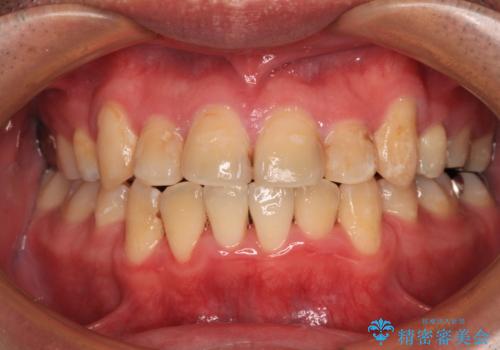

- 上下の八重歯やデコボコを気にして来院された患者様です。

上下ともに八重歯が顕著であったので、上下左右第一小臼歯4本を抜歯し、ワイヤー装置にて矯正治療を行うこととしました。

結婚式をきっかけに矯正治療を決意したとのことでしたが、挙式までの期間があまりにも短かったために、結婚式後に治療を開始することとなりました。